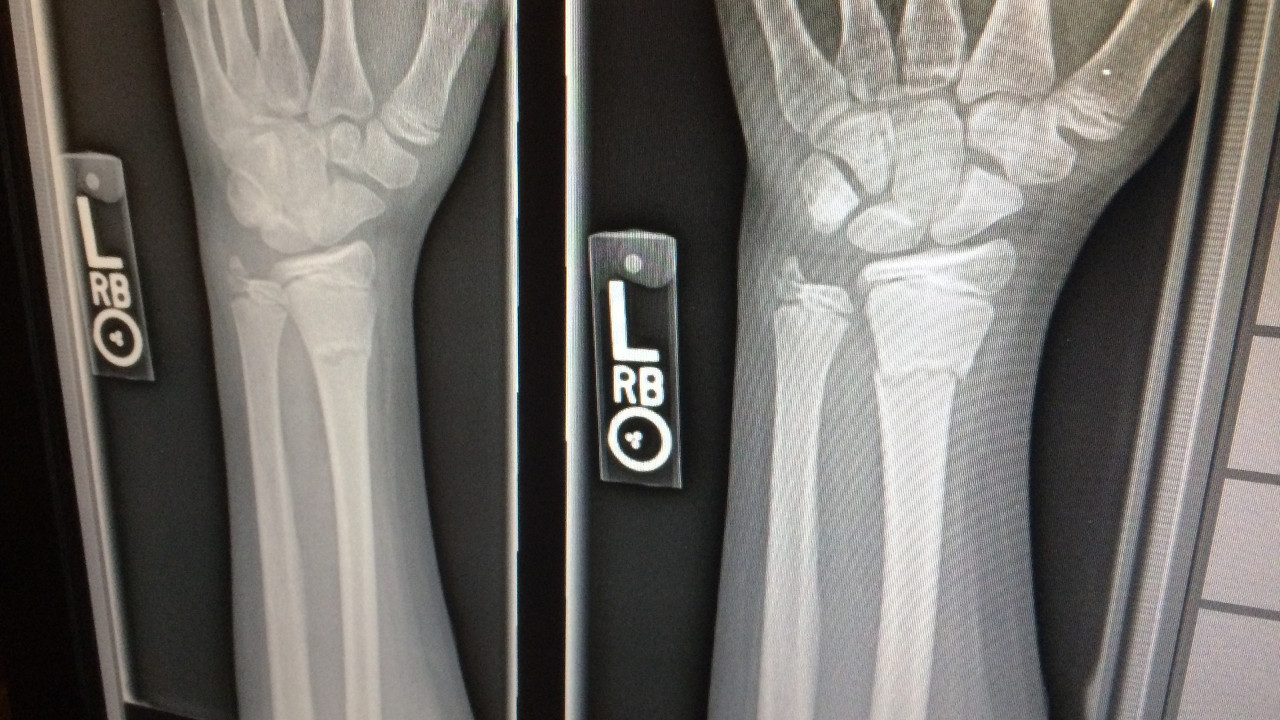

Hastasının ön kolunda kemiğe yakın bir Kalaşnikof mermisini gösteren röntgenini NFT sayesinde dijital sanat eseri olarak satışa sundu.